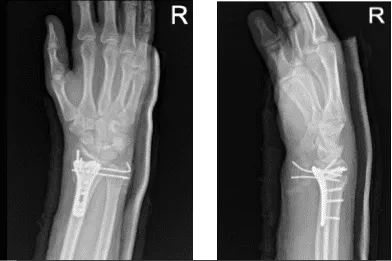

After one-week post-operative the patient was advised to return with X Ray results. Result was presented and discussed the surgically treated fracture of the right wrist. He is doing well and will continue the long arm splint.

Right wrist X-ray 3 or more views-1st week post operative